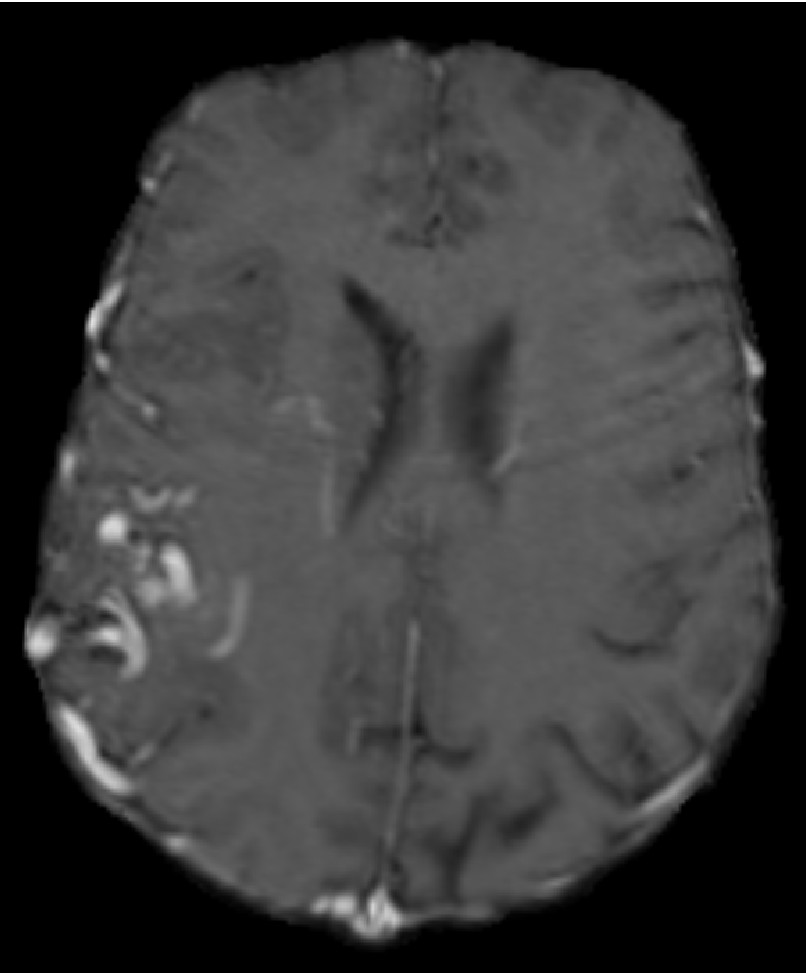

The mesh fidelity is qualitatively evaluated on AVM data (case 3). For this purpose, the AVM mesh is first extracted from the multi-material mesh and then superimposed on the AVM segmentation (Figure 22). The closer the mesh surface is to the boundary of the segmented AVM image, the higher the fidelity. The LD method achieves high fidelity because it completely resolves the vessels (it creates a voxelized mesh surface). Nevertheless, Figure 22e indicates a small shift in the output mesh in relation to the input image, most likely due to image resampling. CLEAVER resolves most of the vessel structures, but the generated mesh is noticeably shifted (Figure 22d). CBC3D achieves satisfactory fidelity. CBC3D’s mesh topological checks are turned off to avoid further red-green subdivisions, keeping the element count low.

Refer to caption

(a) AVM image

(b) CBC3D

(c) CGAL

(d) CLEAVER

(e) LD

(f) PODM

Figure 22: Qualitative evaluation on the fidelity of AVM mesh. Figures LABEL:sub@AVMFidelityOne- LABEL:sub@AVMFidelityFive depict the AVM mesh (red) superimposed on the AVM segmentation (blue). The closer the mesh surface is to the boundary of the segmented material, the higher the fidelity.